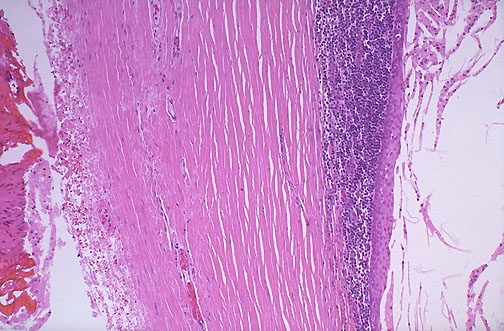

Microscopically, branchial cleft cysts are lined by benign stratified squamous epithelium and are often surrounded by lymphoid tissue, as seen here.